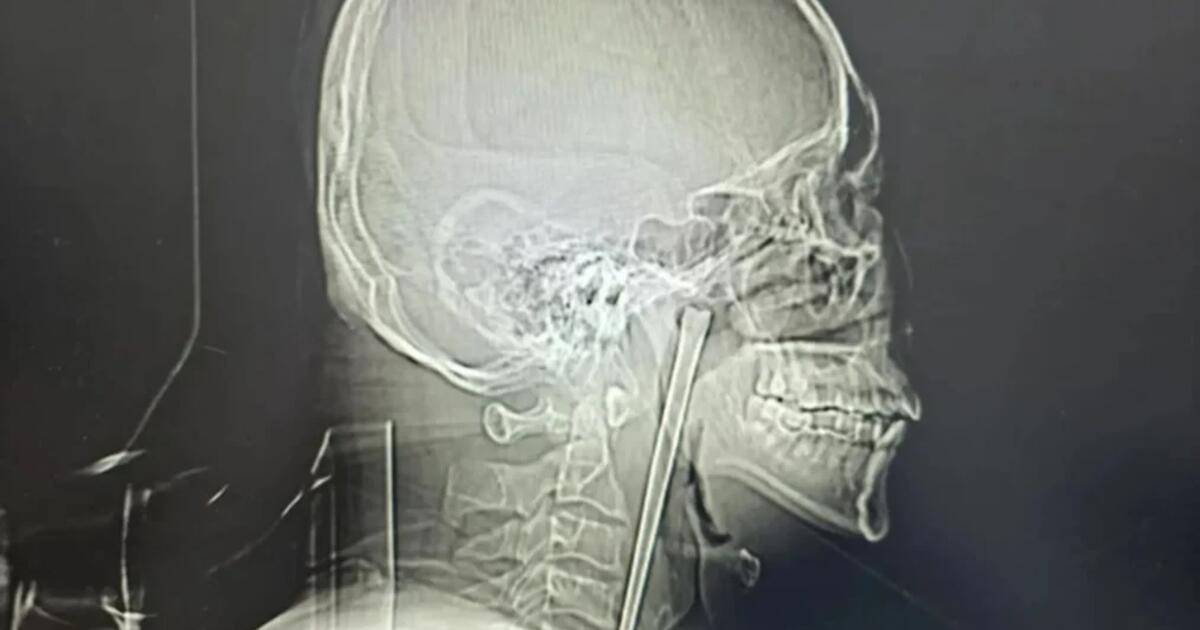

Ο άνδρας, ο οποίος κατονομάζεται μόνο ως κ. Γουάνγκ, πήγε για εξετάσεις λίγο αφότου κατάπιε το ξυλάκι μήκους 13 εκατοστών το 2018, αλλά αρνήθηκε να του το αφαιρέσουν, σύμφωνα με μια μελέτη νοσοκομείου που δημοσιεύθηκε τον Μάρτιο.

Ο 46χρονος Γουάνγκ δεν ήθελε τότε οι γιατροί να του ανοίξουν τον λαιμό με τομή, κι έτσι έζησε με αυτό το παράξενο αντικείμενο – και μαζί με τη δυσφορία – επί χρόνια, όπως ανέφερε η South China Morning Post.

Οι χειρουργοί πραγματοποίησαν μια ελάχιστα επεμβατική πράξη για να αφαιρέσουν το αντικείμενο μέσω του στόματος του Γουάνγκ, αντί να κάνουν τομή στον λαιμό του, σύμφωνα με την αναφορά του νοσοκομείου.

Οι φωνητικές του χορδές και ο γειτονικός βλεννογόνος ευτυχώς δεν τραυματίστηκαν και λειτουργούσαν φυσιολογικά μετά την επέμβαση, σύμφωνα με την αναφορά.